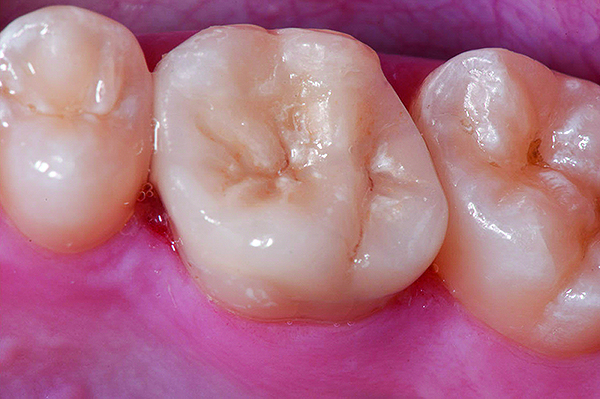

More translucent versions are now used in the posterior region as full-contour or monolithic all-zirconia restorations. Marketed first in this category was BruxZir® (Glidewell Laboratories, www.bruxzir.com), with many other manufacturers subsequently entering the market (Figure 15 and Figure 16).

Fig 15. Machined CL-IIIb zirconia framework prior to coloration and final sintering (Fig 15); colorized and final sintered monolithic CL-IIIb zirconia restoration (Fig 16) (images courtesy of Enrico Steger/Zirkonzahn).

Figure 15

Fig 16. Machined CL-IIIb zirconia framework prior to coloration and final sintering (Fig 15); colorized and final sintered monolithic CL-IIIb zirconia restoration (Fig 16) (images courtesy of Enrico Steger/Zirkonzahn).

Figure 16

CL-IIIb high-strength 100% crystalline ceramics initially were alumina-based materials (eg, Procera®, Nobel Biocare, www.nobelbiocare.com); more recently they are zirconia-based (eg. LAVA™, 3M ESPE, www.3MESPE.com; Prettau®, Zirkonzahn, www.zirkonzahn.com). Alumina systems have proven successful for single units but are being replaced by zirconia and lithium disilicate due to the increased risk of failure in the molar region.25,26 Zirconia can also be used when significant tooth structure is missing, when high risk for flexure and stress is present, for posterior full-crown and fixed partial denture situations (Figure 13 and Figure 14), and when adhesive bonding is problematic, such as with subgingival margins.

In cases where the bond and seal cannot be maintained (ie, high-risk bonding situations, including moisture control problems, high shear and tensile stresses on bonded interfaces, and variable bonding interfaces), high-strength CL-III ceramics or metal ceramics (CL-IV, see below) are appropriate, because they can be placed using conventional cementation techniques. A concern with full-contour zirconia, however, is wear on opposing dentition.27

Whether alumina or zirconia, these materials demonstrate greater strength than CL-I and CL-II materials and can be used to fabricate a core substructure to replace metal. However, they are more opaque due to their greater crystalline content, which detracts from overall esthetics. They are therefore layered with porcelain,28 allowing these materials to offer both superior strength and improved esthetic results.28 CL-III high-strength ceramics require a thickness of 1.2 mm to 1.5 mm, depending on the substrate color.20,26